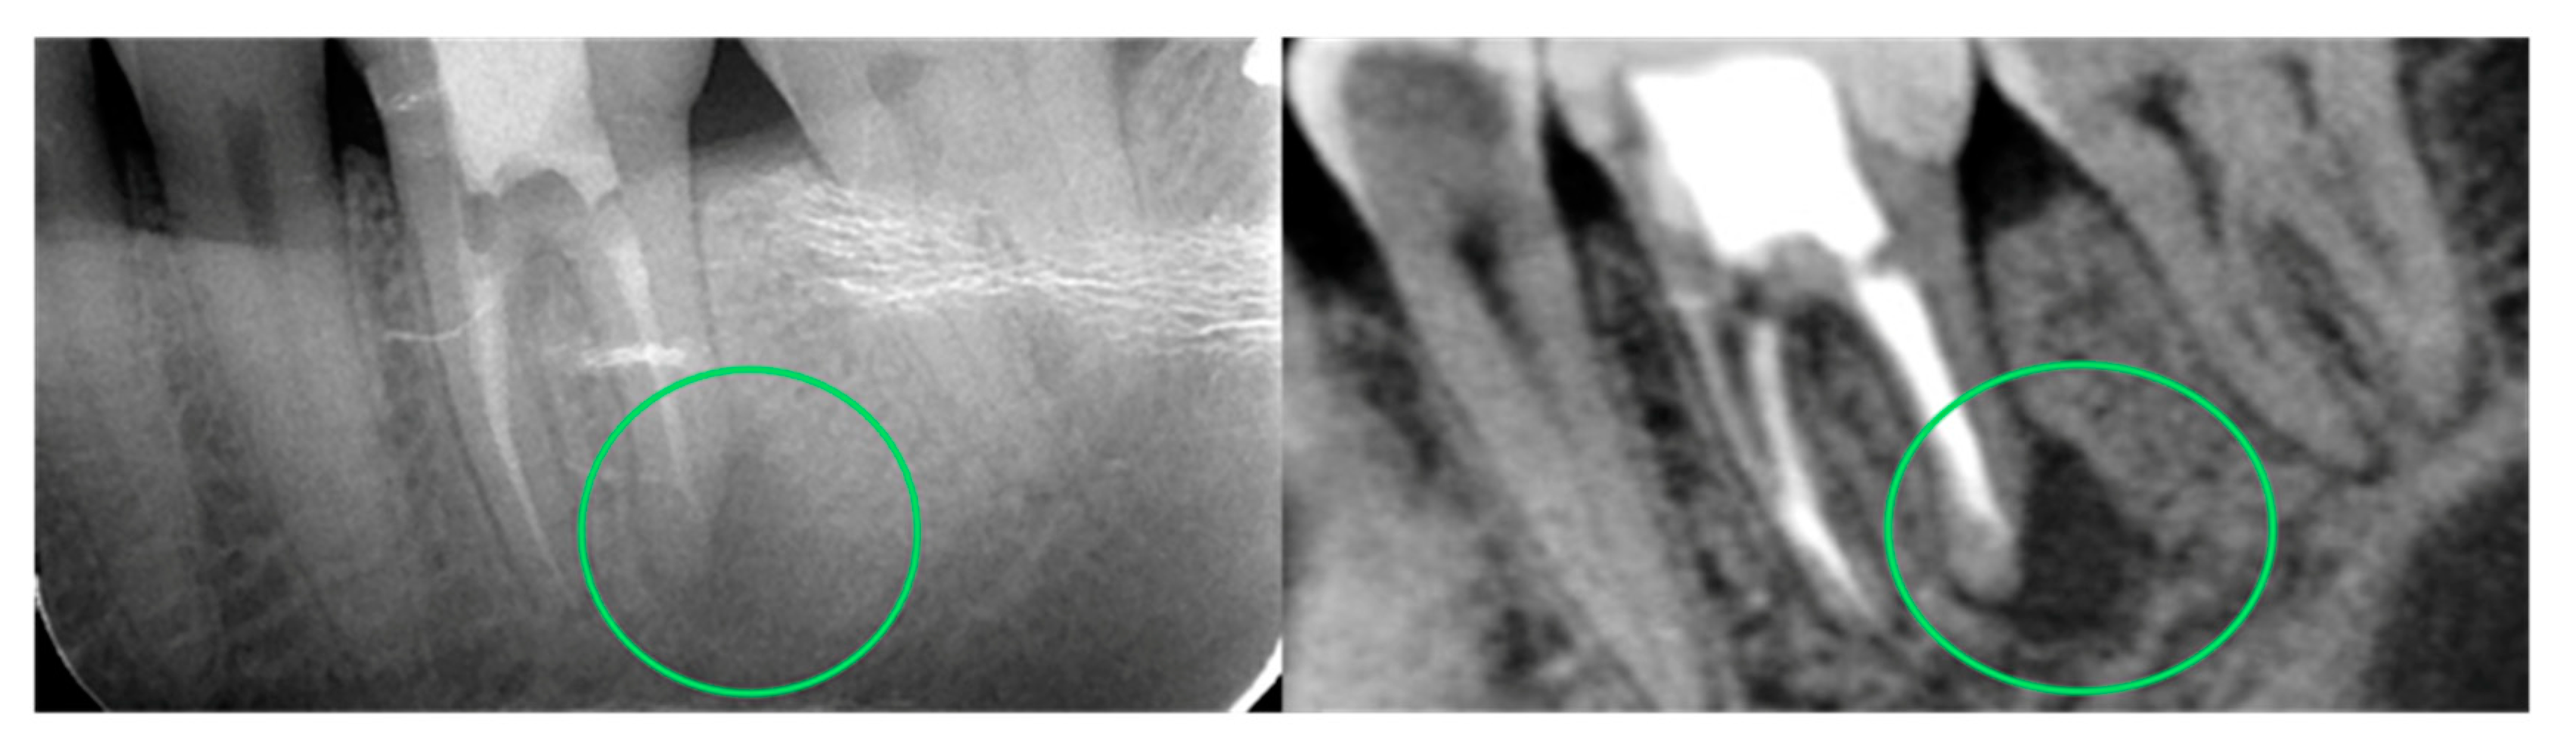

- Zhang, C.; Fan, L.; Zhang, S.; Zhao, J.; Gu, Y. Deep learning based dental implant failure prediction from periapical and panoramic films. Quant. Imaging Med. Surg. 2023, 13, 935–945. [Google Scholar] [CrossRef]